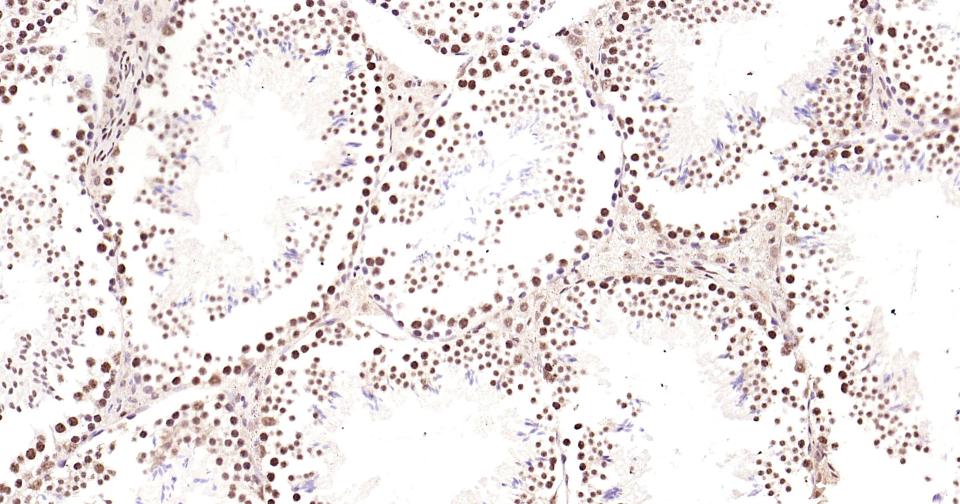

Paraformaldehyde-fixed, paraffin embedded Rat Testicles; Antigen retrieval by boiling in sodium citrate buffer (pH6.0) for 15 min; Antibody incubation with Phospho-CREB-1 (Ser133) Monoclonal Antibody, Unconjugated(bsm-61105R) at 1:200 overnight at 4°C, followed by conjugation to the bs-0295G-HRP and DAB (C-0010) staining and DAB (C-0010) staining.